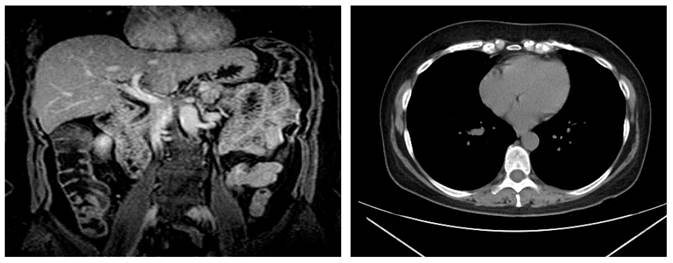

During the patient’s follow-up, laboratory tests were performed to rule out associated diseases that could cause hyperamylasemia (Table 1). She also underwent an endoscopy in which a duodenal biopsy was performed, which in turn showed glandular architecture associated with chronic nonspecific infiltrate, intraepithelial lymphocyte count <40/100 epithelial cells, without atrophy. Besides, during colonoscopy diverticula were observed in the sigmoid colon. Regarding imaging studies, no lymphadenopathies were evidenced on a CT of the neck (soft tissue), and evidence of cancer was observed in the CT scan of the chest, abdomen and pelvis (Figure 1); likewise, a normal biliary tract and no signs of choledocholithiasis were evidenced during magnetic resonance cholangiopancreatography (Figure 2). Further tests included ACCR (0.02%) and a confirmation test for macroamylasemia, which was positive (Table 2). The patient was asymptomatic during her evaluation at the outpatient department.